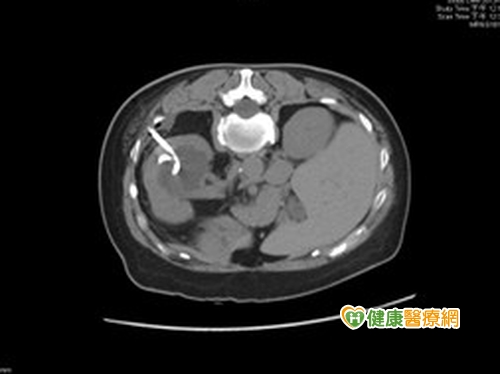

一位年近60歲的王姓婦人,日前因慢性咳嗽就醫,結果在進行電腦斷層檢查時,竟發現輸尿管有結石,已將輸尿管阻塞,且合併有嚴重的腎臟水腫;經由泌尿科醫師治療,才將輸尿管結石及管阻塞的問題一次處理好。醫師提醒,泌尿道結石不能放任不管,以免小病成大病,若治療無效時,有相當高的致死率,不得不慎!